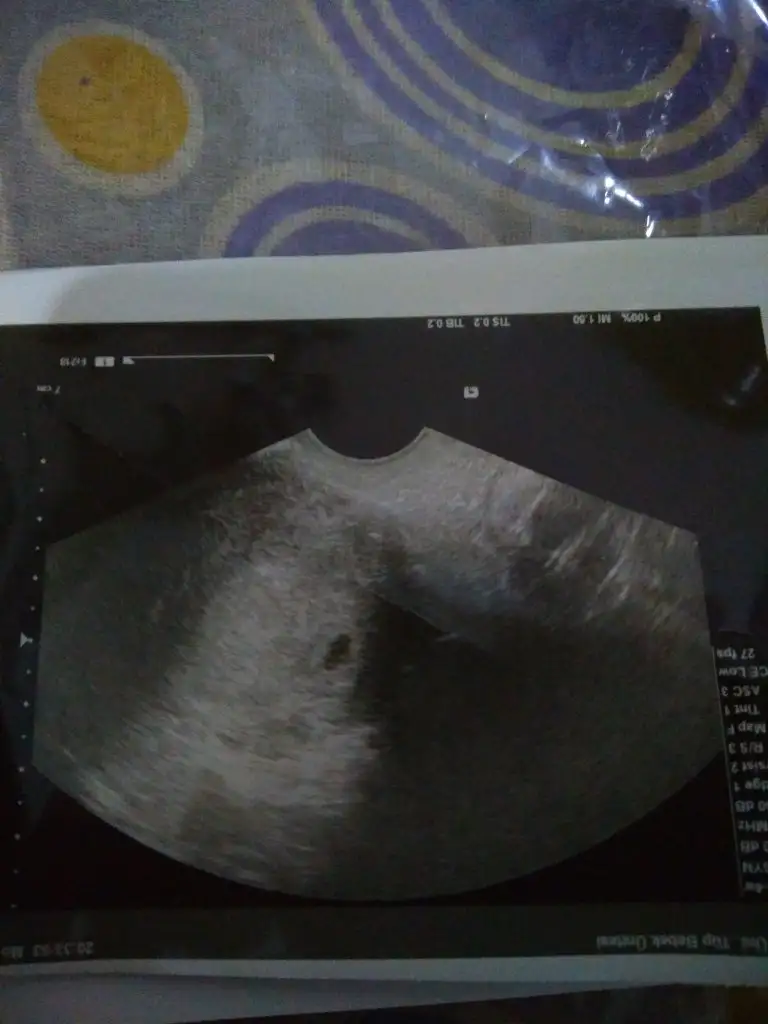

Bugün hastaneye gittim, elimden geldiğince tüm önlemlerini aldım. Hastane bomboştu ve çok titiz çalışılıyordu. Girişte ateş olcumü yapildi. Normalde tıklım tiklim olan tüp bebek bölümünde ben dahil 2 kişiydik sadece. Allah'a şükür keseyi gorduk bugün. Doktor 2 hafta sonra kalp atışı için çağırdı.

Kizlarrrr....keseyi gördük çok şükür.....doktorum erken yumurtlamissin dedi ben betayı 3000 lerde görünce korkmuştum. Sorun yokmis. Cok sukur. Bin sukur. 10 gün sonraya gel dedi.